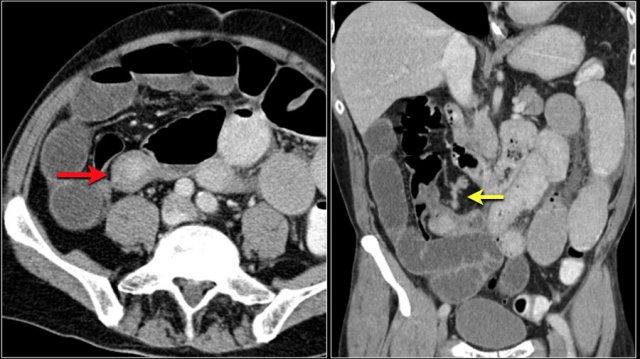

Các hình ảnh cho thấy một khối hình vòng ngắn gây tắc nghẽn ở hỗng tràng (mũi tên vàng) kèm hạch bạch huyết to (mũi tên đỏ).

Kết quả giải phẫu bệnh xác nhận là ung thư biểu mô tuyến.

- Tổn thương hẹp lòng tá tràng do ung thư biểu mô tuyến (mũi tên vàng).

- Không thể phân tách khỏi tụy (mũi tên đỏ).

- Giãn tá tràng trước chỗ hẹp.